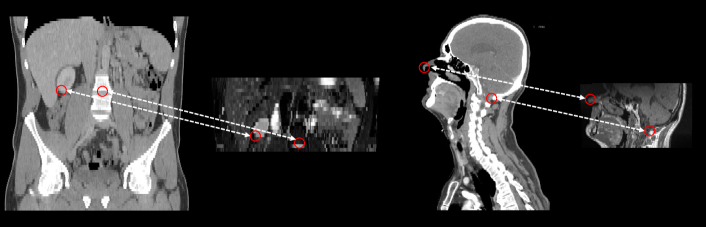

Refer to caption

Fig. 3: Two examples of multi-modality medical images with substantially different FOVs. Left: Abdominal CT and MRI images; Right: Head and neck CT and MRI images. We can achieve the roughly alignment of different images by matching the same anatomical landmarks on them.

This alignment issue can be addressed by exemplar-based landmark detection methods, which include matching sampled points on fixed and moving images followed by automatic image cropping. For single-modality images, SAME-affineLiu et al. (2021); Li et al. (2023) leveraged SAM Yan et al. (2022) to match corresponding points for affine registration, demonstrating impressive robustness in handling FOV differences. For multi-modality images, however, training a SAM-style model with cross-modality capabilities to drive SAME-affine may encounter a chicken-and-egg issue Yin et al. (2022), since, on one hand, we require registered multi-modality images to train SAM and learn the correspondence and, on the other hand, we need the corresponding SAM landmarks for accurate image registration with a large FOV disparity.

2.2 Multi-modality data alignment

The diagnostic accuracy can be significantly enhanced by utilizing the complementary information from aligned multi-modality medical images. A notable example is that the aligned MRI and CT images can empower radiotherapists for precise treatment planning Khoo et al. (2000). Typically, multi-modality medical images are aligned in two steps: a global affine or rigid transformation Mok and Chung (2022); Huang et al. (2021); Hoffmann et al. (2021) and a deformable registration Balakrishnan et al. (2019); Mok and Chung (2020). However, in our experiments, existing affine/rigid registration methods cannot work well when two images have substantially different FOVs (Fig. 3 and  9). In such circumstances, align the correspond body part and crop them into a similar FOV is needed.